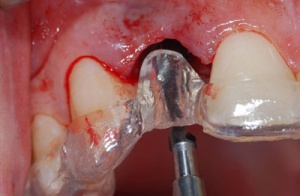

C'est la position spatiale de l'implant qui détermine la qualité de la prothèse en terme fonctionnel, esthétique.

Photos extraites du diaporama :